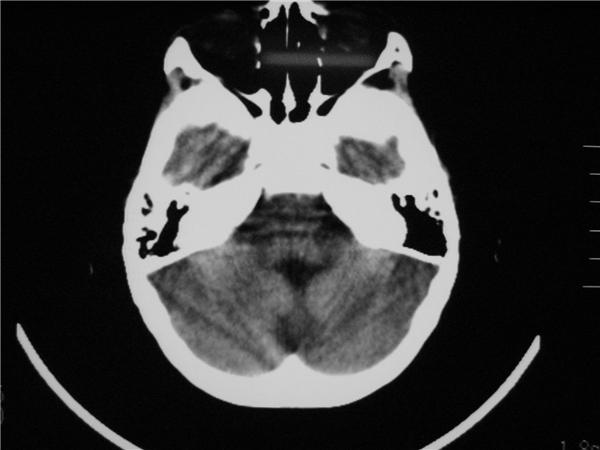

标题: PED2843: CT-23675 F 4Y 大家看看颅内有问题没。 [打印本页]

标题: PED2843: CT-23675 F 4Y 大家看看颅内有问题没。

四脑室扩大,三脑室稍扩大上移

四脑室扩大,,六脑室

四脑室扩大,密度降低,图像的问题?建议mr扫描。